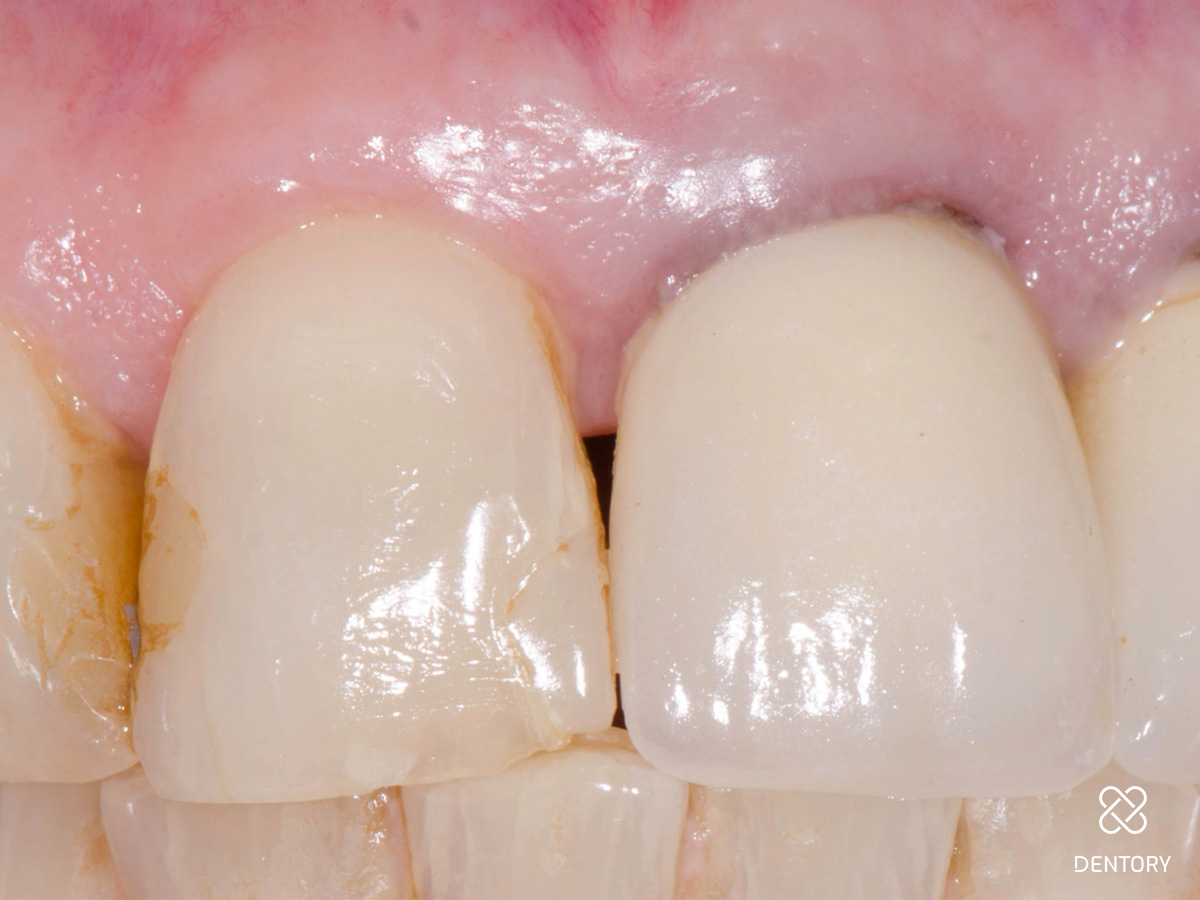

Abbildung 5

Einprobe an 22:Nach Abnahme der Provisorien werden die Stümpfe gereinigt und die Kronen einprobiert. Hier ist die Einprobe der Krone 22 zu sehen.